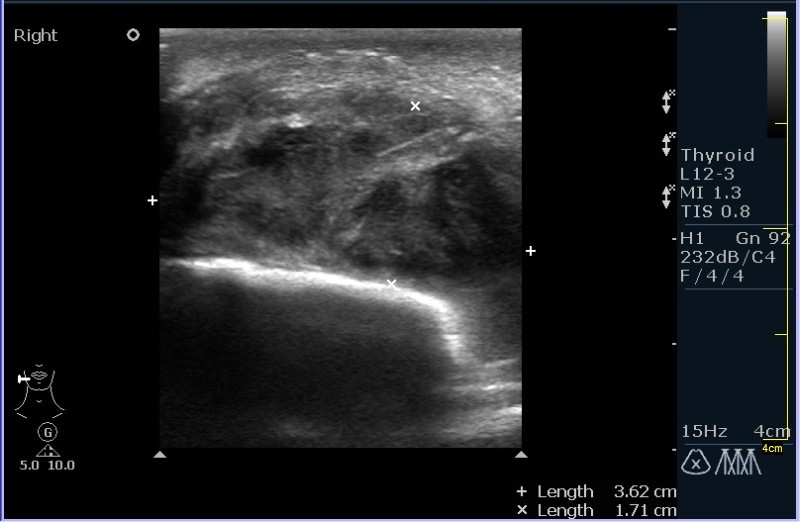

УЗИ области правой околоушной железы и угла нижней челюсти.

Девочка 8 лет, с опухлостью щеки и области правого угла нижней челюсти, резко боезненной при пальпации. В анамнезе (после наводящих вопросов :ugeek: ), визит к стоматологу около месяза назад.